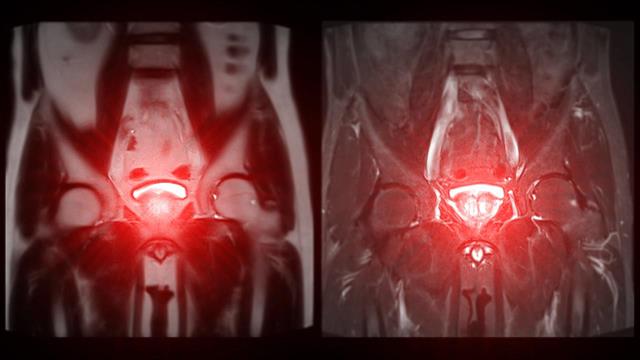

Εντυπωσιακά ήταν τα αποτελέσματα της μελέτης KEYNOTE-905/EV-303 για την περιεγχειρητική θεραπεία ασθενών με μυοδιηθητικό καρκίνο ουροδόχου κύστης που δεν δύνανται να λάβουν εισαγωγική θεραπευτική αγωγή που να περιλαμβάνει σισπλατίνη.

Γνωρίζουμε πως περίπου το 50% των ασθενών με μυοδιηθητική νόσο δεν μπορούν να λάβουν την καθιερωμένη θεραπευτική αγωγή με σισπλατίνη σύμφωνα με τα κριτήρια του Galsky καθώς μπορεί να είναι ηλικιωμένοι, σε επιβαρυμένη κλινική κατάσταση και με επηρεασμένη νεφρική η καρδιολογική λειτουργία.

Αυτός ο πληθυσμός ασθενών οδηγείται απευθείας στο χειρουργείο έχοντας περιορισμένες θεραπευτικές επιλογές. Η χορήγηση περιεγχειρητικής θεραπείας με το σύζευγμα αντισώματος-φαρμάκου ενφορτουμάμπη βεντοτίνη (enfortumab vedotin) σε συνδυασμό με ανοσοθεραπεία με πεμπρολιζουμάμπη (pembrolizumab) μείωσε κατά 60% των κίνδυνο υποτροπής έναντι μόνο του χειρουργείου στους ασθενείς αυτούς.